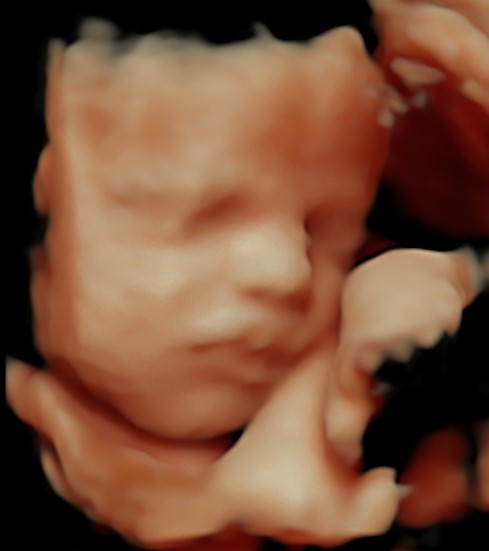

4D/5D/HD Ultrasound Gallery

Gallery